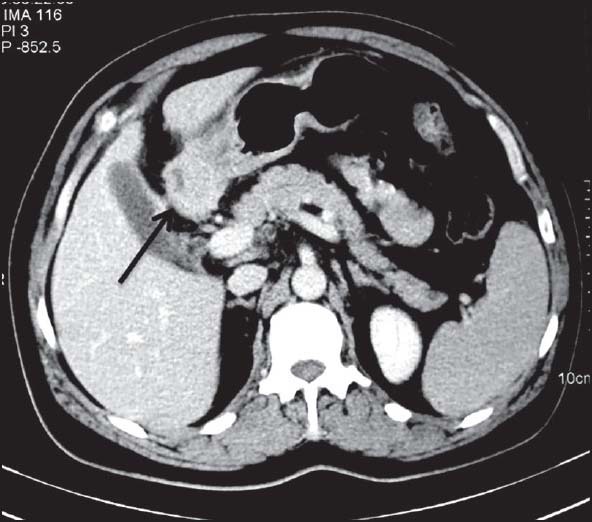

| Figure 3:Duodenal gastrointestinal stromal tumors in a 45-year-old male — (a) barium meal follow through spot image showing widening of C-loop of duodenum with mucosal irregularity (arrowhead) and ulcerations (b) coronal contrast-enhanced computed tomography image showing heterogeneously enhancing mass lesion in second part of duodenum (white arrowhead) having intraluminal as well as subserosal component without proximal obstruction

| Figure 3:Duodenal gastrointestinal stromal tumors in a 45-year-old male — (a) barium meal follow through spot image showing widening of C-loop of duodenum with mucosal irregularity (arrowhead) and ulcerations (b) coronal contrast-enhanced computed tomography image showing heterogeneously enhancing mass lesion in second part of duodenum (white arrowhead) having intraluminal as well as subserosal component without proximal obstruction